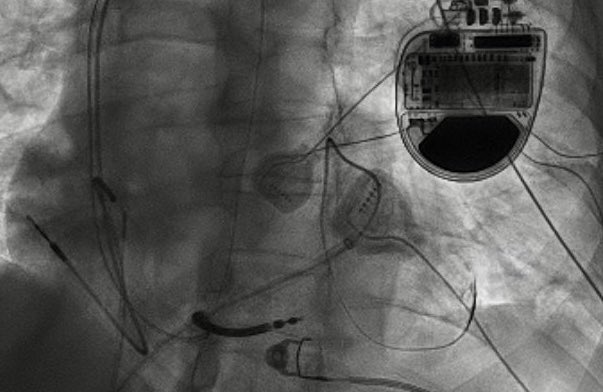

Question for EP fellows: Elderly M with dual ICD.

Incidental or Iatrogenic VF? What programming feature is shown here? How do you fix? #Epeeps @EvanBlankMD @FaisalMMerchant @melchami99 @narrowQRS @rdschaller